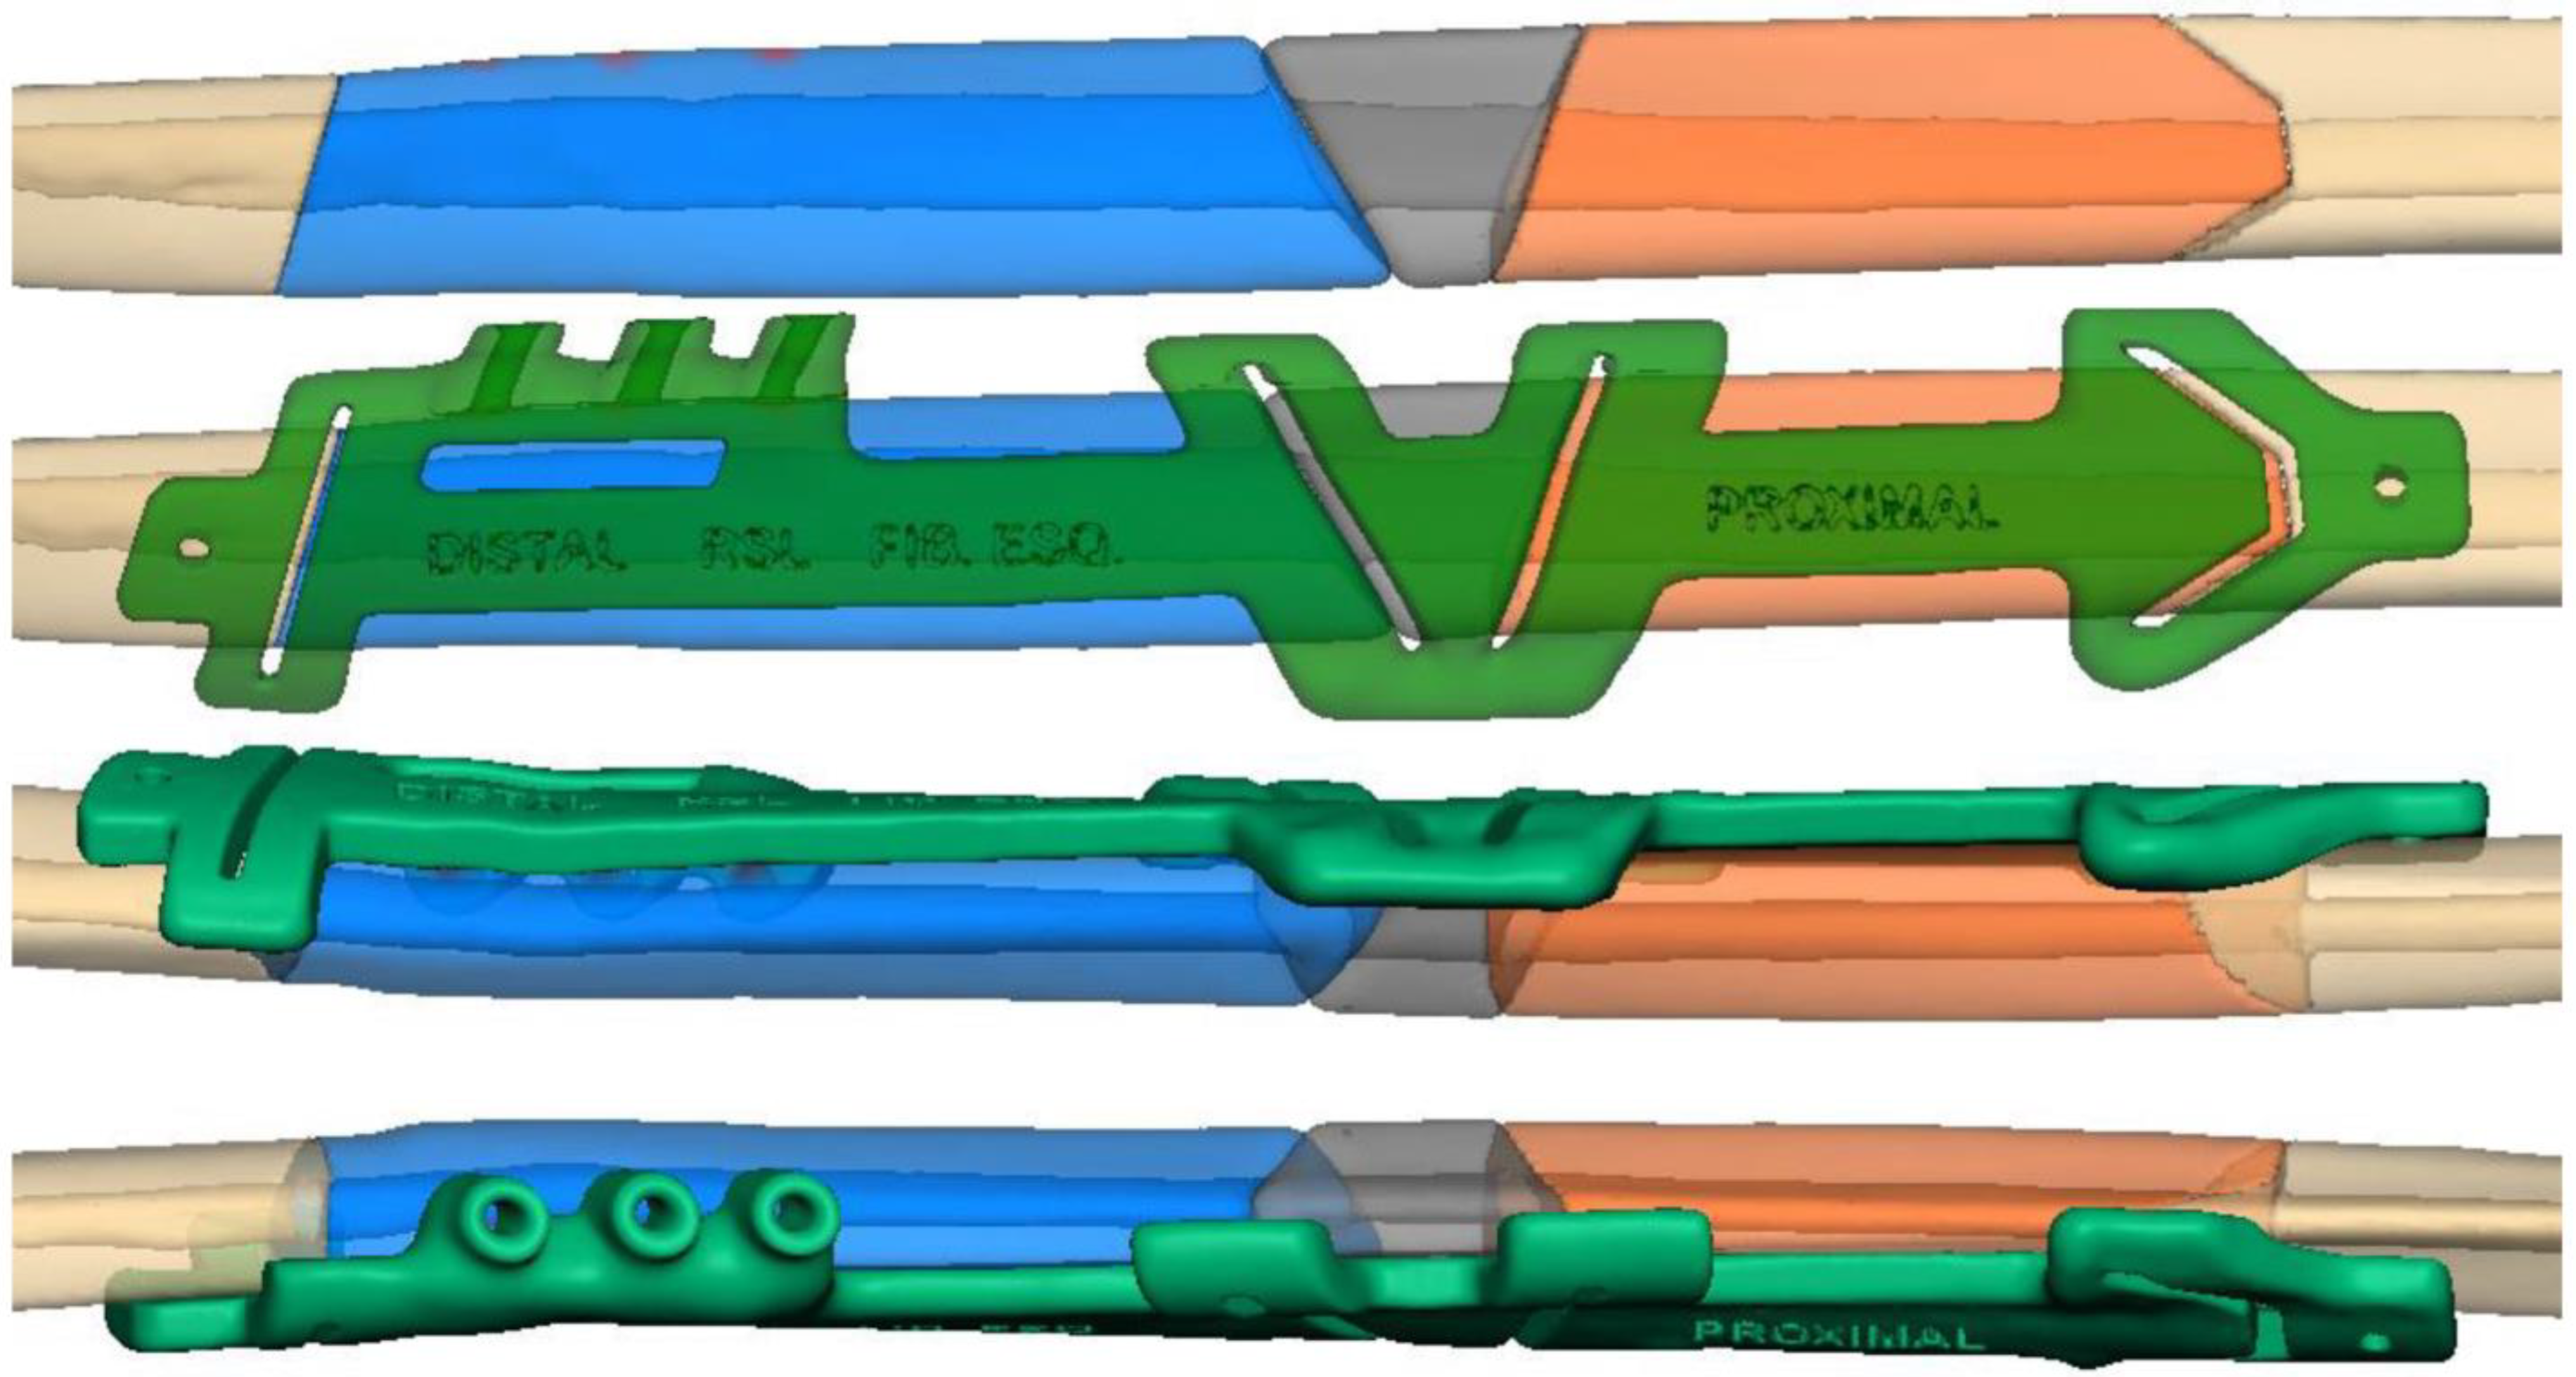

2.1. Case 1

2.2. Case 2